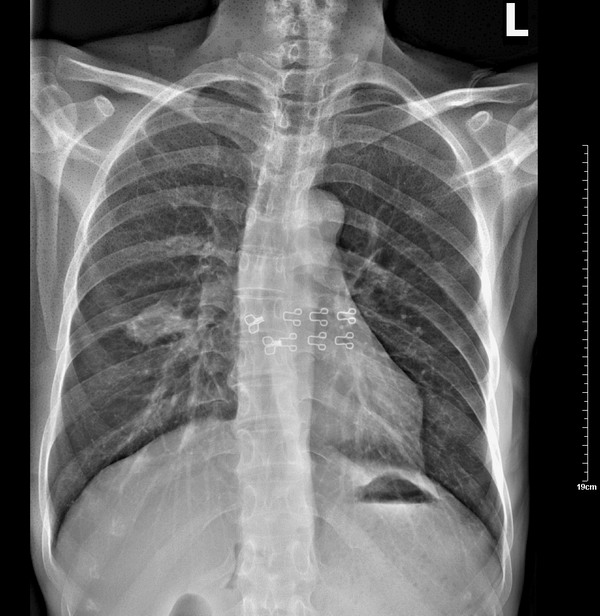

x7532。右肺病变,结果是:右下叶背段肺结核。

患者最后是在省肺科医院考虑为肺结核。实际上痰检并没有找到抗酸杆菌。但以抗结核治疗病变明显好转。

下面是2009年10月26日的片子: